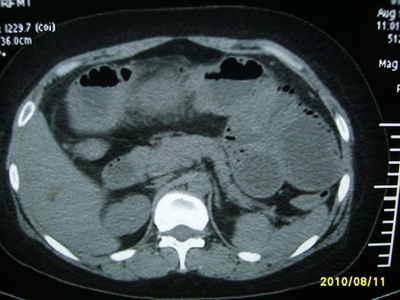

5天前突发腹痛剧烈难忍,伴解淡血水样便。近一天来腹痛缓解,没有明显的腹膜炎的体征。今天照的腹部ct。从ct上看感觉是一个绞窄性肠梗阻,但是现在没有腹痛。不好解释

要有麻烦了,感觉小肠有套叠还有扭转改变,估计部分已有坏死。

高位肠梗阻(不全性),原因小肠(空肠)扭转,肠壁水肿增厚,成年人肠梗阻要排除合并占位,建议手术。

绞窄性肠梗阻_肠管套叠 扭转,肠壁明显水肿。

支持绞窄性肠梗阻,肠壁明显水肿并见有多发小泡状积气--肠坏死

考虑绞窄性肠梗阻并肠坏死。